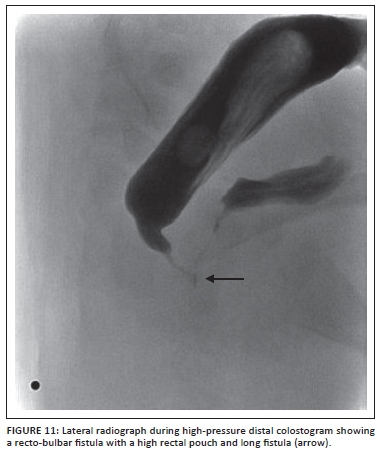

A Foley catheter is then inserted into the distal fistula and 3 ml of saline is injected into the balloon. Gentle traction is applied to the catheter to create a seal so that adequate pressure can be applied when injecting the contrast. A radio-opaque marker is placed where the anus should be. Contrast medium (water soluble) is injected via the Foley catheter with a 50 ml catheter tip syringe into the rectum under gentle but increasing pressure until the distal rectum and fistula are identified. The AP view is pivotal to see how much distal bowel is present, and the lateral view then defines the distal rectal anatomy as it relates to the urinary tract. Fluoroscopy with spot filming with the child in AP and then lateral position is performed. Sufficient pressure must be applied to distend the distal rectum adequately and identify the fistula.

It is worth noting that too much pressure may cause bowel perforation or decrease the actual distance from distal rectum to skin, giving the impression of a falsely low pouch. However, too little pressure will give the false impression of a high rectum with no fistula; this will show up as a flattening of the distal rectum at the pubococcygeal line, and means more pressure is required for an accurate study. In most cases where there is not a fistula to the bladder, the study will be considered completed once contrast has reached the level below the pubococcygeal line, indicating that enough pressure has been applied. The sacrum, coccyx, perineum and bladder must all be visible during fluoroscopy. If a fistula is identified, it is suggested to continue injecting the contrast until the bladder fills and the baby spontaneously voids. If this is the case, valuable information regarding the urinary tract can be obtained. It is in essence a modified MCUG14 (Figures 8- 10).

The information that the surgeon would like to know is the precise location of the fistula in relation to the urinary tract, the length of bowel available for the pullthrough procedure, and the relationship between the sacrum, coccyx and rectum. All this information is vital to plan the type of operation required (PSARP, laparotomy or laparoscopy).9 The usual surgical approach for a bulbar or low prostatic fistula would be PSARP. For a vesical or high prostatic fistula, the approach would normally be laparotomy or laparoscopy for ligating the fistula and mobilising the bowel, then a limited PSARP incision to bring it down to the cutaneous junction in the centre of the muscle complex. It must be emphasised, however, that not every patient fits this formula, and one may find a low prostatic fistula that has a long fistula with a rectal stump that is high. Such a patient would do best with a laparotomy/laparoscopy first, followed by a limited PSARP (Figure 11).